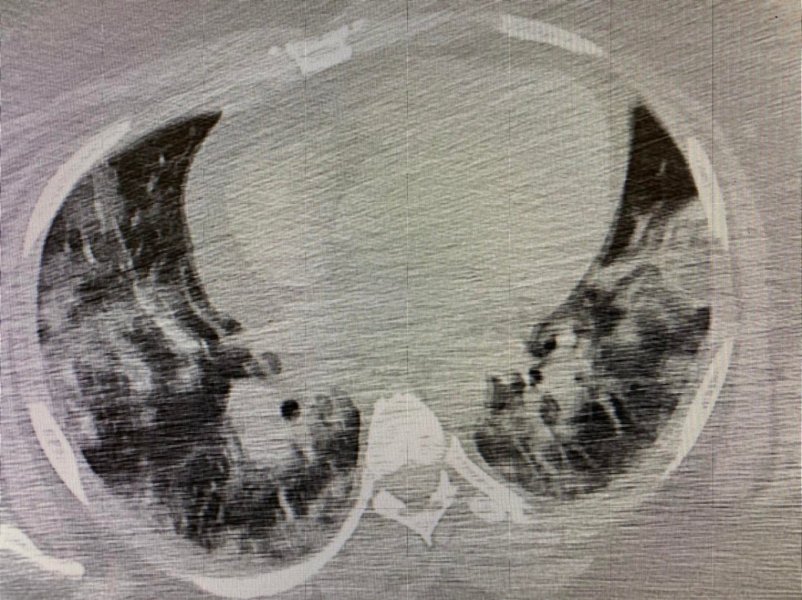

Dziewięciu było zaszczepionych. Na moją szczególną uwagę zwróciło jedno podwójne przyjęcie. 50 letni ojciec z 30 letnim synem mieszkający w jednym gospodarstwie domowym. Ojciec zaszczepiony dwiema dawkami szczepionki, syn nie został zaszczepiony. W TK klatki piersiowej. 50-letni Pacjent po szczepieniu - zmiany w płucach 1%, 30-letni syn bez szczepienia - zmiany w płucach 50%. Jest to jeden z wielu przykładów pokazujący, że szczepienia są ważne i należy się szczepić.

1 zdjęcie: 1% zajętych płuc.

2 zdjęcie: 50% zajętych płuc.